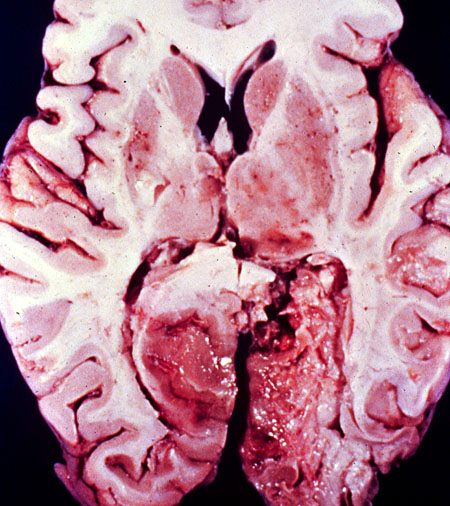

Brain, gross, infarct, uncal herniation

Bilateral symmetrical infarct of posterior cerebral arteries, secondary to bilateral uncal herniations compressing posterior cerebral arteries.